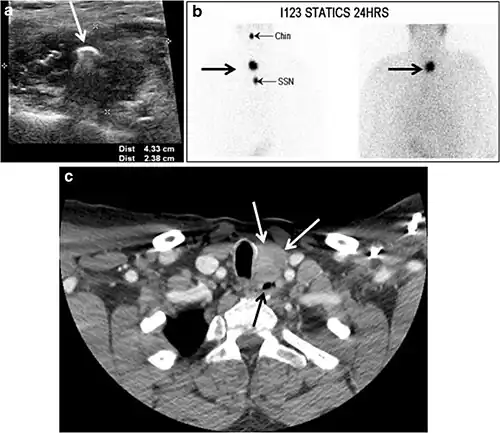

The likelihood of positive anatomic imaging is greater when serum Tg is >10 ng/mL. A diagnostic CT scan adds additional value to neck US in detecting central compartment macro-metastases in the mediastinum and retro-tracheal area. According to the recent American Thyroid Association guidelines, an upper chest and neck CT scan with IV contrast should be obtained when: 1) neck US is inadequate in visualizing possible local nodal disease (high Tg, negative neck US, and RAI imaging); 2) US is not able to delineate the disease completely, as in the case of bulky recurrent nodal disease; or 3) evaluation of possible recurrent invasive disease is needed (Figs. 7, 88 and and9).9). CT scans are also the most sensitive diagnostic tool for the detection of pulmonary micro-metastases. Many of the neck US features that are considered as suggestive signs of disease recurrence are also applicable to CT examination. These signs might include sizable rounded nodules in the thyroid bed, fine calcifications, or cystic change.[1]

Ectopic thyroid tissue may be detected in the tongue near the foramen cecum (90%) and along the midline between the thyroid isthmus and posterior tongue, lateral neck, mediastinum, and oral cavity. The most frequent location is the base of the tongue (Figs. 16, 1717 and and18).18). In 70% of cases, the ectopic thyroid is the only functional thyroid tissue present in the body (Fig. 18).[1]